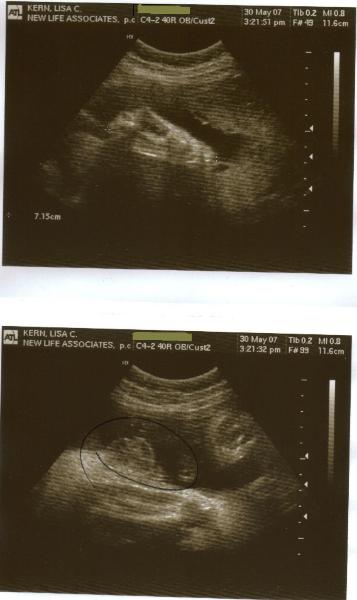

12-5-06

Well, we finally decided it's time to tell

everyone.  On November 18th, we found out

Lisa's pregnant.  Today (12-5-06) we went for

a preliminary ultrasound due to some

concerns we had been having.  It turns out

everything is OK and our estimated due date

is 16 days off!  So according to the baby's

size, we'll be nine weeks pregnant tomorrow.

We were really excited to see the heartbeat!  It

looks like baby will be here around July 11,

2007.